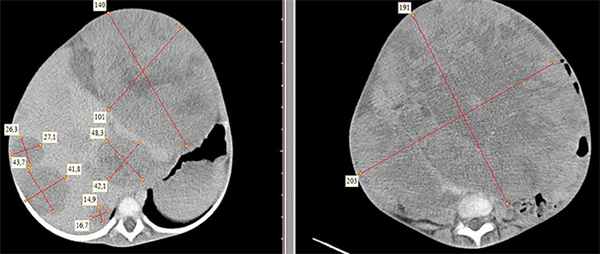

![KT 1]()

Рисунок 1. КТ брюшной полости ребенка с большой нефробластомой с метастазами в печень.

![KT 2]()

Рисунок 2. КТ: опухоль при поступлении. Клинически: при пальпации опухоль в проекции правой почки до 12 см в диаметре. Общеклинические исследования в пределах возрастной нормы. При КТ органов брюшной и грудной полости: КТ-картина объемного образования правой почки без признаков интрапульмональных метастазов (см. рис. 2). УЗИ брюшной полости: в проекции правой почки солидно-кистозное образование 101ґ114ґ99 мм, объемом 500 мл, васкуляризация активная, интактная часть почки 57ґ12ґ40 мм. Объемное образование правой почки — опухоль Вильмса. Предварительный диагноз: опухоль Вильмса правой почки, 2-я стадия.